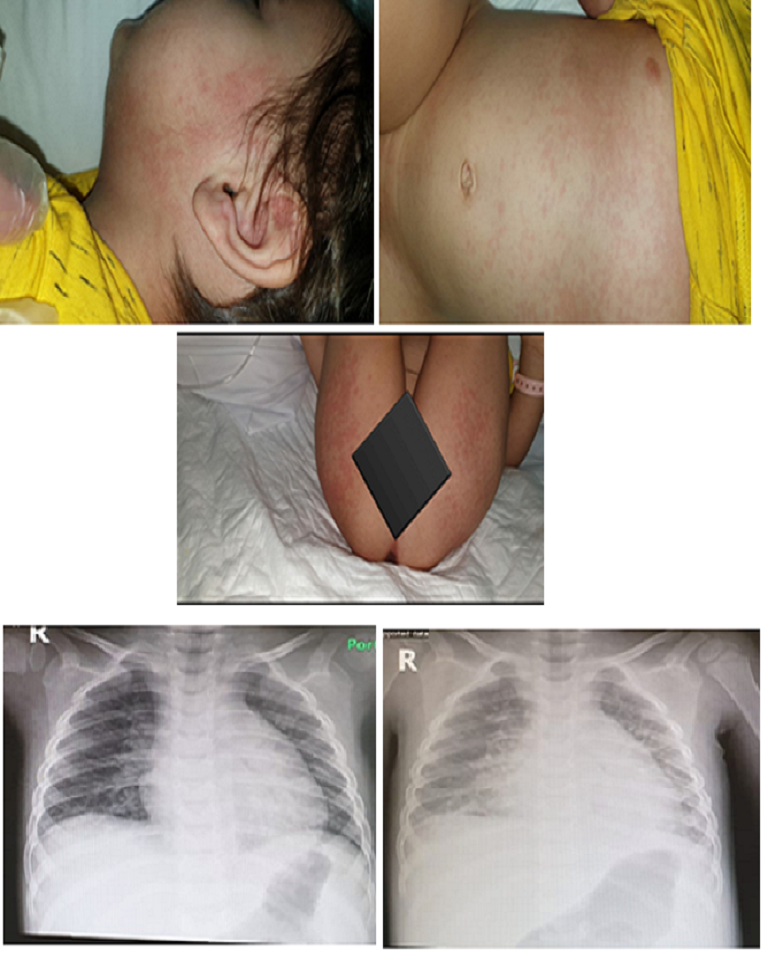

Multi-System Inflammatory Syndrome in Children (MIS-C) Reported in COVID-19 Positive 2.5-Year Old Boy

Ammar Muhammad Alyousef, Mohammad Abdulkhaliq Alshamrani, Abdulaziz Sayah Alruwaili, Amer Farhan Aldmak, Waleed Ahmad Okash

International Journal of Innovative Research in Medical Science·September 2, 2020